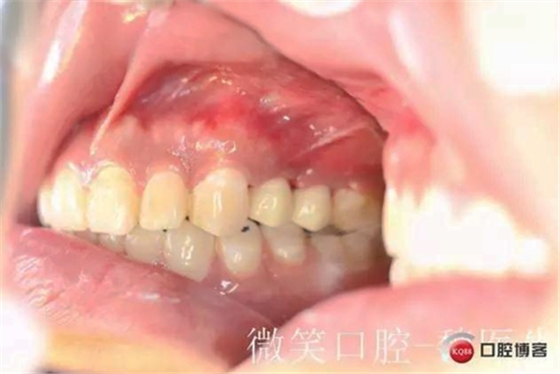

7天復(fù)診拆線情況,五號(hào)牙纖維樁+樹脂核后直接牙體預(yù)備四號(hào)牙樹脂充填。

6號(hào)牙的近中鄰面大約磨去1MM左右

取模(常規(guī)要求冠延長(zhǎng)后最少3個(gè)月取模,老外要求六個(gè)月,真是沒有辦法患者時(shí)間太緊張。)